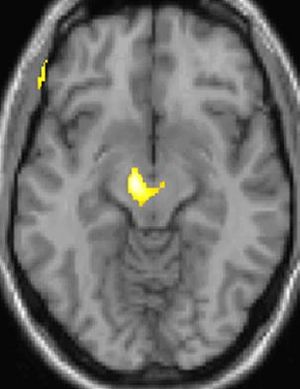

PET 스캔

PET 스캔에 의한, 군발 두통 발생 중에 활발해진 뇌 부분을 나타내는 그림.

양전자 방출 단층 촬영술(PET) 이미지 1: 통증 중 활성화되는 뇌 영역

실제로 양전자 방출 단층 촬영술(PET) 스캔 연구 결과, 군발 두통 발작 중에 통증이 없을 때와 비교하여 시상하부의 특정 영역이 활성화되는 것이 관찰되었다. 또한, 복셀 기반 형태 계측법(VBM)을 이용한 연구에서는 군발 두통 환자와 그렇지 않은 사람 사이에 뇌 구조를 비교했을 때, 시상하부의 일부 영역에서 구조적인 차이가 발견되기도 했다.[35] 이러한 영상 연구 결과는 시상하부가 군발 두통의 발생과 관련이 깊다는 가설을 뒷받침한다.